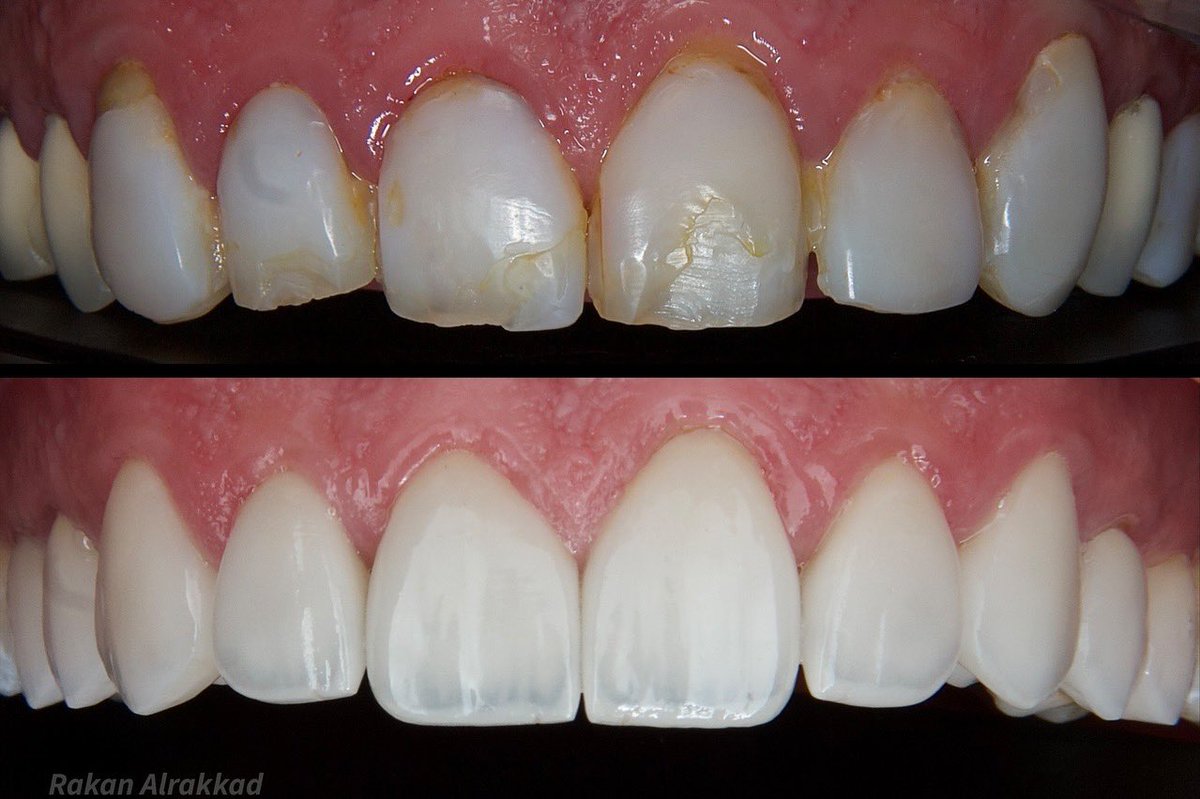

The small detail makes a difference Root canal treatment + post & core E-MAX crowns 👑 All procedures done under rubber dam 🦷

The small detail makes a difference

Root canal treatment + post & core

E-MAX crowns 👑

All procedures done under rubber dam 🦷